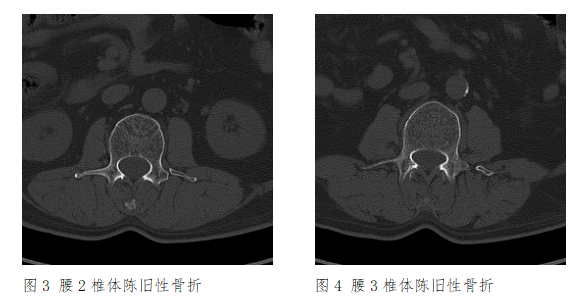

XXX医院CT(2017-7-3)示:L2、L3左侧横突骨折,断端骨皮质局部连续,断端圆钝、硬化,提示陈旧性骨折。

XXX人民医院CT(2017-7-10)示:L2、L3左侧横突陈旧性骨折。

根据检验所见赖XXL2、L3左侧横突骨折,断端骨皮质局部连续,断端圆钝、硬化,结合案情分析认为,赖XX腰2、3椎体左侧横突骨折系本次外伤前即存在的陈旧性骨折,且骨折时间较长,与本次外伤无直接因果关系,不宜据此进行损伤程度鉴定。横突新鲜性和陈旧性骨折在CT片上的区别主要根据断端形态,一般横突新鲜性骨折,断端锐利,骨折线清晰,而横突陈旧性骨折一般断端有愈合,若分离较大至骨不连,断端会呈现圆钝、硬化改变。

图5 腰2、3椎体陈旧性骨折